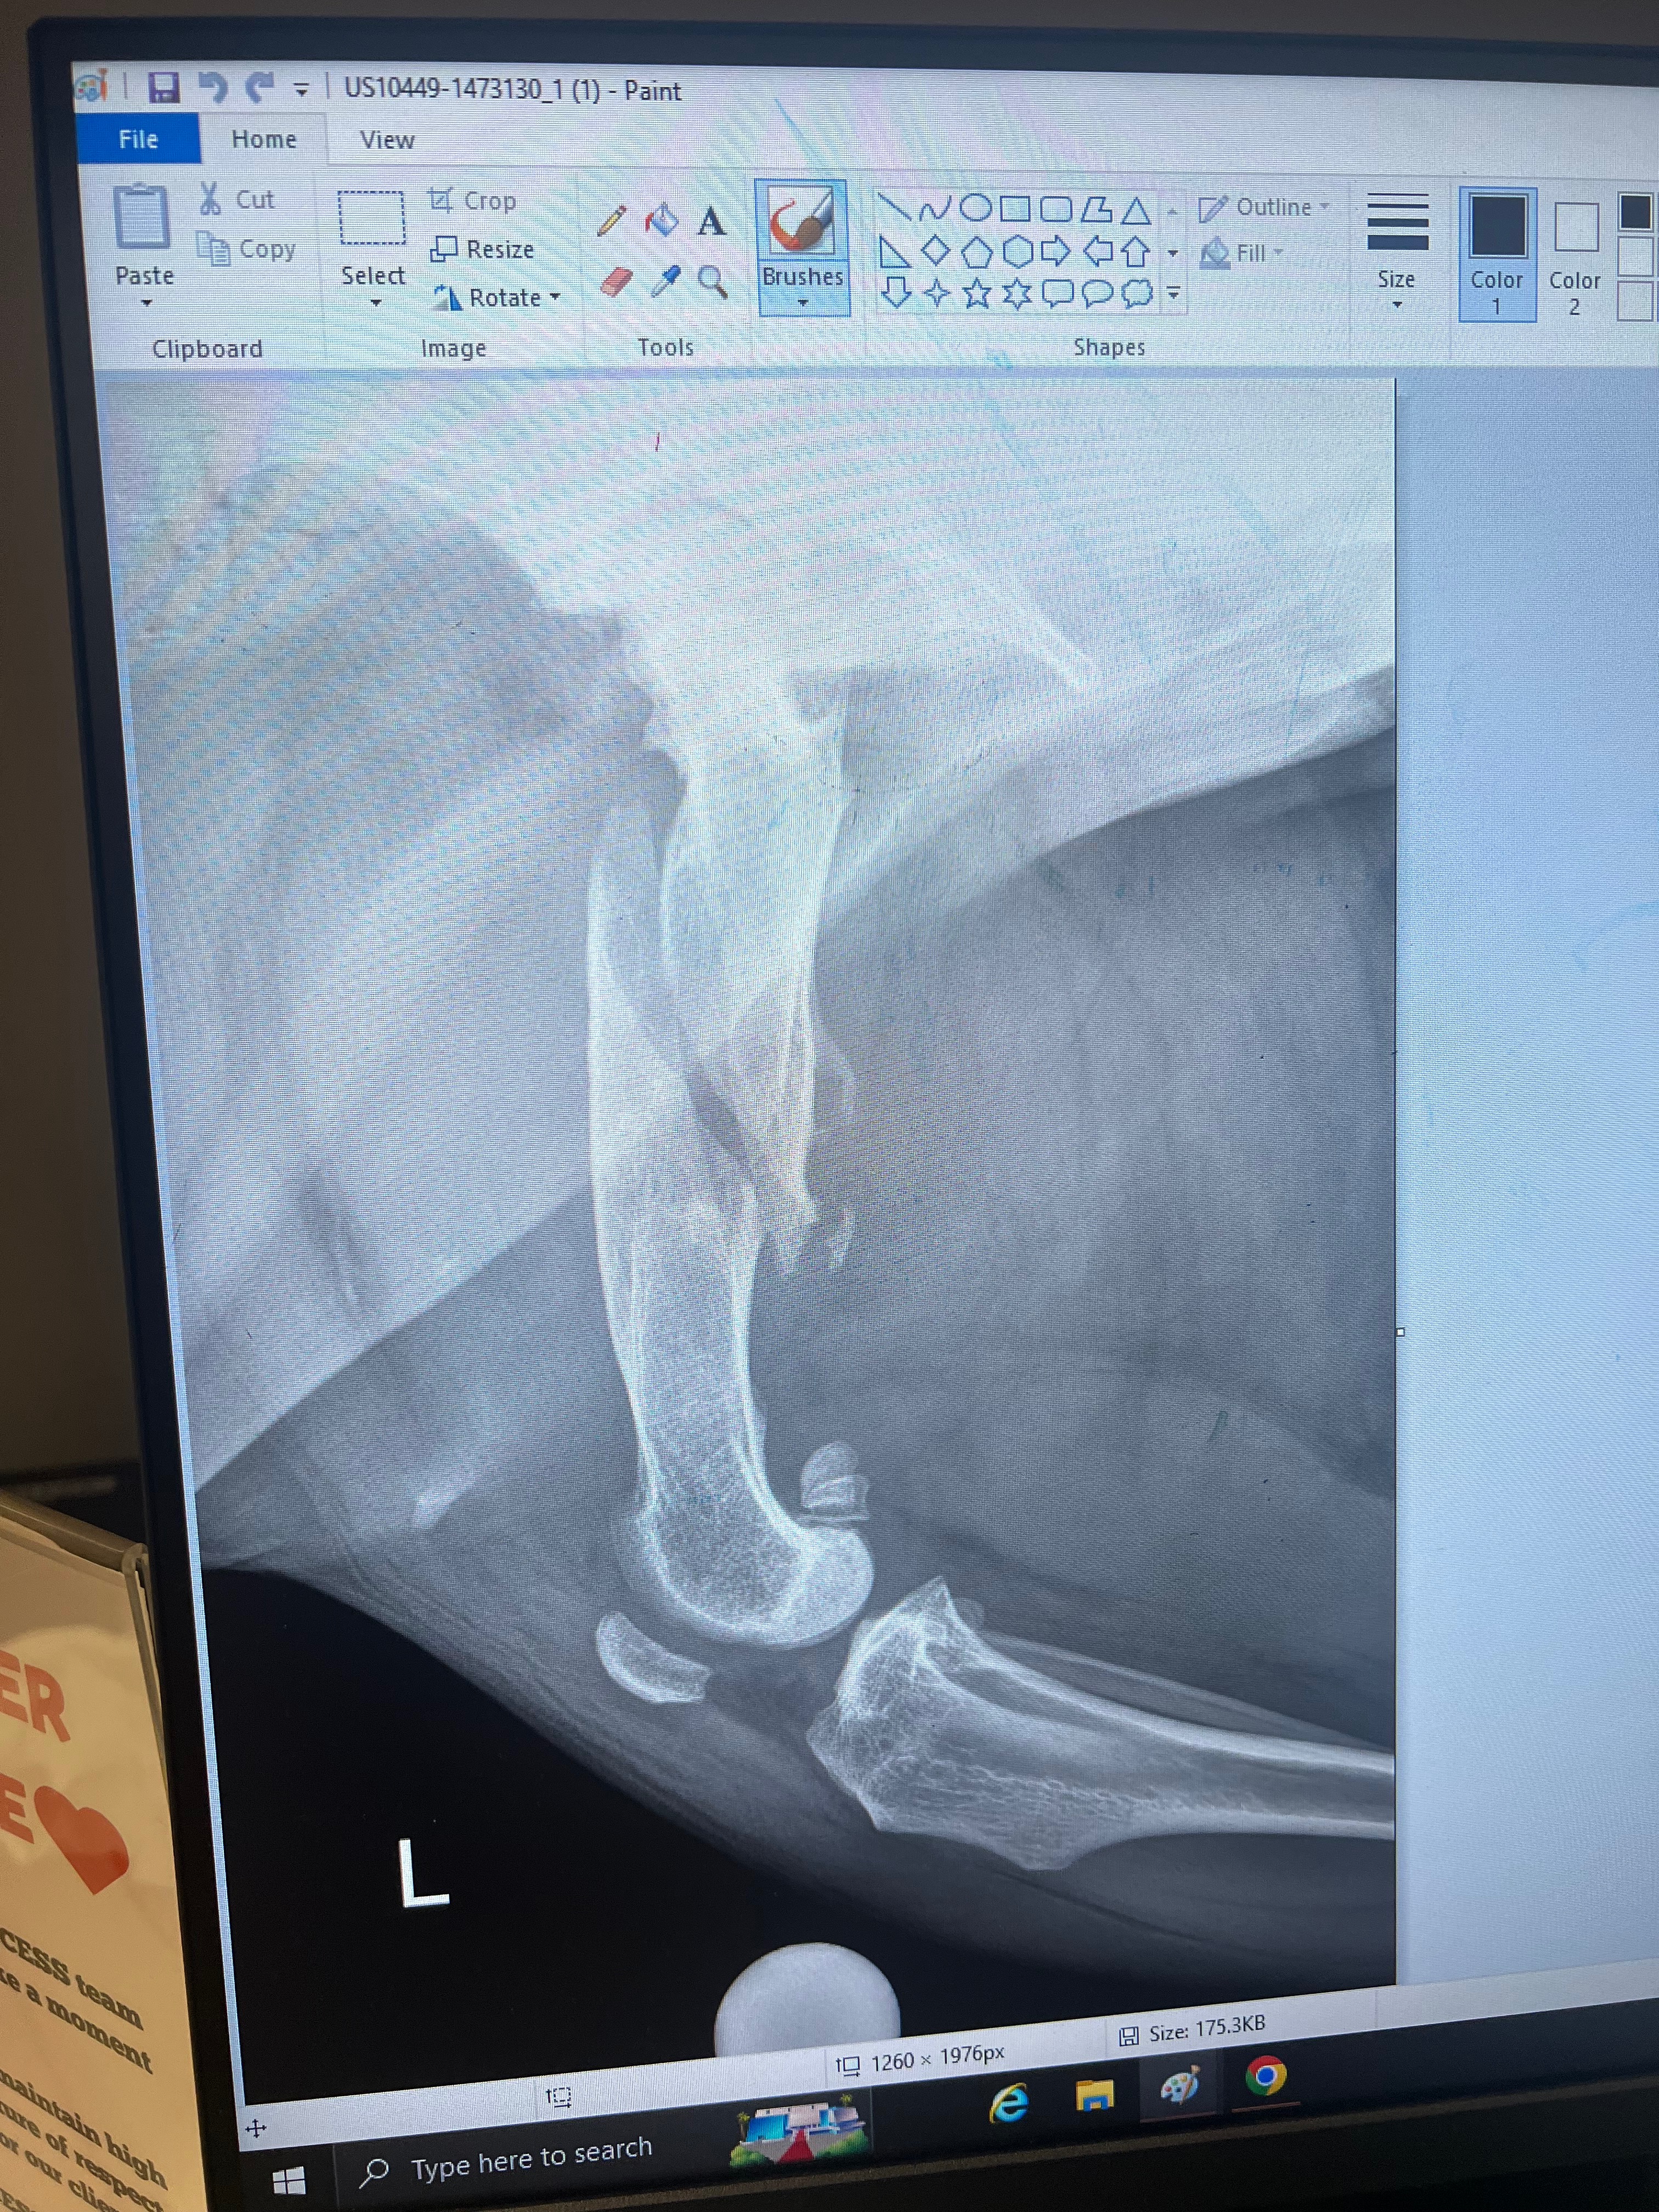

On Sunday, Tank and Peaches got into a scuffle by our front door, and somehow her leg got caught on something, and she broke her femur completely in half. Unfortunately, it was probably a matter of time before she needed another surgery just because all of her legs and bones are so weak from the previous injuries she had suffered from before we adopted her. She is such a survivor and a fighter that she was still trying to walk, even though her leg has been dangling since Sunday. We took her to the surgeon today, and it was confirmed on X-ray that her femur is literally broken in half. There is no other option other than to have her go into surgery immediately tomorrow morning to place a rod in her femur. Her recovery is going to be long, but we know we are in good hands with the surgeon at Access Culver City because he has done both dogs' knee surgeries, as well as that hospital saved my bearded dragon's life when he was suffering from a terrible infection. We definitely deserve a plaque there with how much money we have spent on our furry and scaly babies, lol. But in all seriousness, we had to pay for the surgery upfront, which we really cannot afford and had to take out loans and credit cards to make it work. The surgery is going to cost $10,700 total. We hate asking for any financial help and never want to feel like a burden, but we know how much people care about our animals and know how much we do for them. We would appreciate any amount at all so we can continue caring for the Jarrell Farm fully. Thank you in advance ❤️